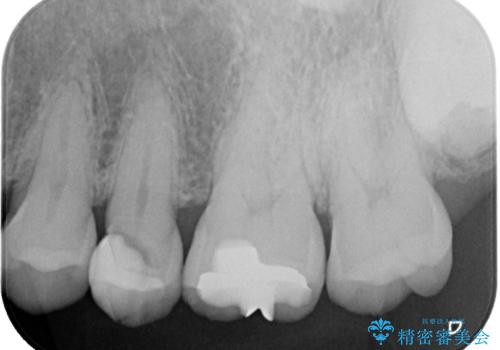

精密検査を行ったところ、上顎左側第二小臼歯のインレー(詰め物)が欠け、その内部に虫歯が進行している状態でした。幸いにも虫歯は神経まで達しておらず、神経を残した治療が可能と判断しました。

欠損範囲が大きかったため、オールセラミッククラウンによる補綴治療を行いました。